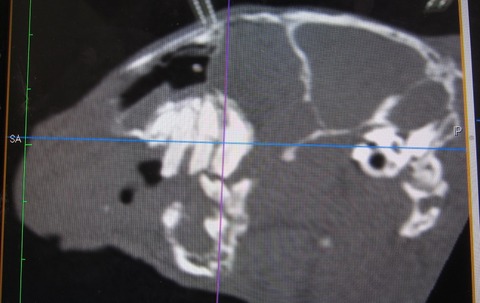

途中経過をCTで

まだまだたくさん残ってますが、👆これが👇こうなります。